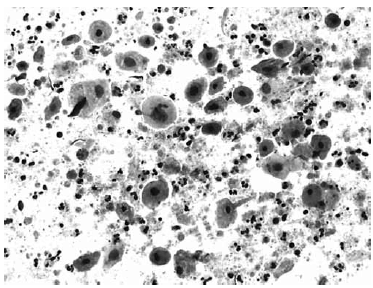

Nas questões de números 46 a 60, assinale a alternativa que melhor corresponde ao diagnóstico do quadro microscópico apresentado.

Adenocarcinoma endometrial.